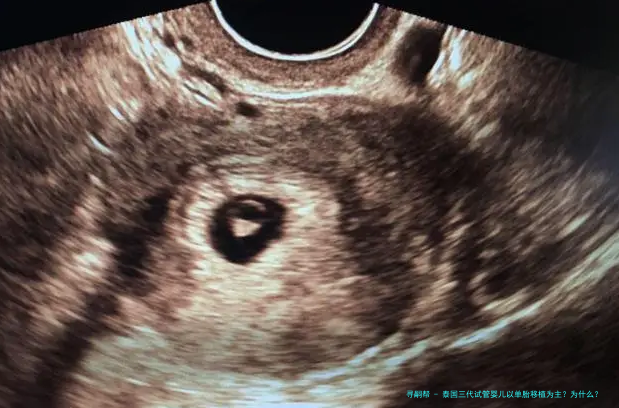

泰国三代试管婴儿以单胎移植为主?为什么?

随着多个胎儿条件的放开,女年纪的增长,很多家庭去泰国做试管婴儿,因为要的是多胎,在进行胚胎移植的时候建议移植了一个胚胎。如此,泰国三代试管婴儿以单胞胎移植为主?为什么?下方跟随来一起了解一下吧。

单胎移植、双胎移植具体情况具体分析,泰国医生并不是盲目建议试管婴儿家庭都进行双胎移植。

对于条件理想的患者,括移植2个有可能双胎妊娠的患者,或者因体重、子宫异常不能承受双胎妊娠的这么一部分患者,一般是建议进行单囊胚移植,既能保证她们的妊娠率,也能减低期的各种风险。

对于条件稍差的患者。比如:高龄、巢储备差,或者患子宫肌瘤、腺肌症等情况的患者,这些不利因素会影响胚胎着床率。那么,在这种情况下,会移植2个胚胎增加女方怀的机会。但,若是后期出现问题,从安全的因素考虑,请务必减胎。